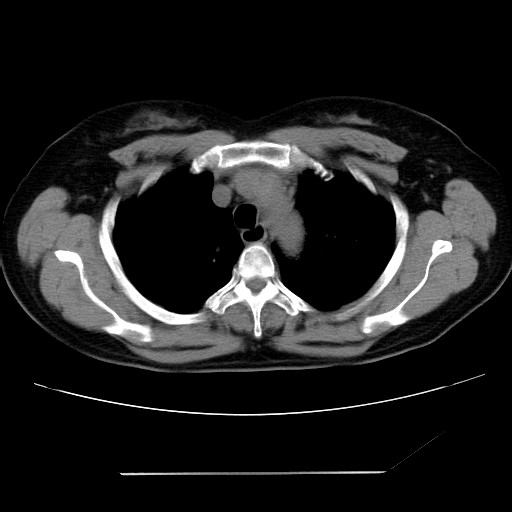

标题: CT24018:女性,62岁,咳嗽4年,无热,胸部CT扫 [打印本页]

女性,62岁,长期咳嗽,既往从事工作有粉尘接触,有高血压病史,110/150mmhg,近日咳嗽加重,脸面浮肿,请大家帮看下,

1、尘肺;2、慢性支气管炎合并肺部感染;3、心影增大(左房、左室大),考虑高血压性心脏病。

能否考虑是尘肺引起的肺源性心脏病?

慢支并肺部炎症;右肺结核球?主肺动脉、右肺动脉影不宽,右心室不大,不支持肺心病;无心包积液。